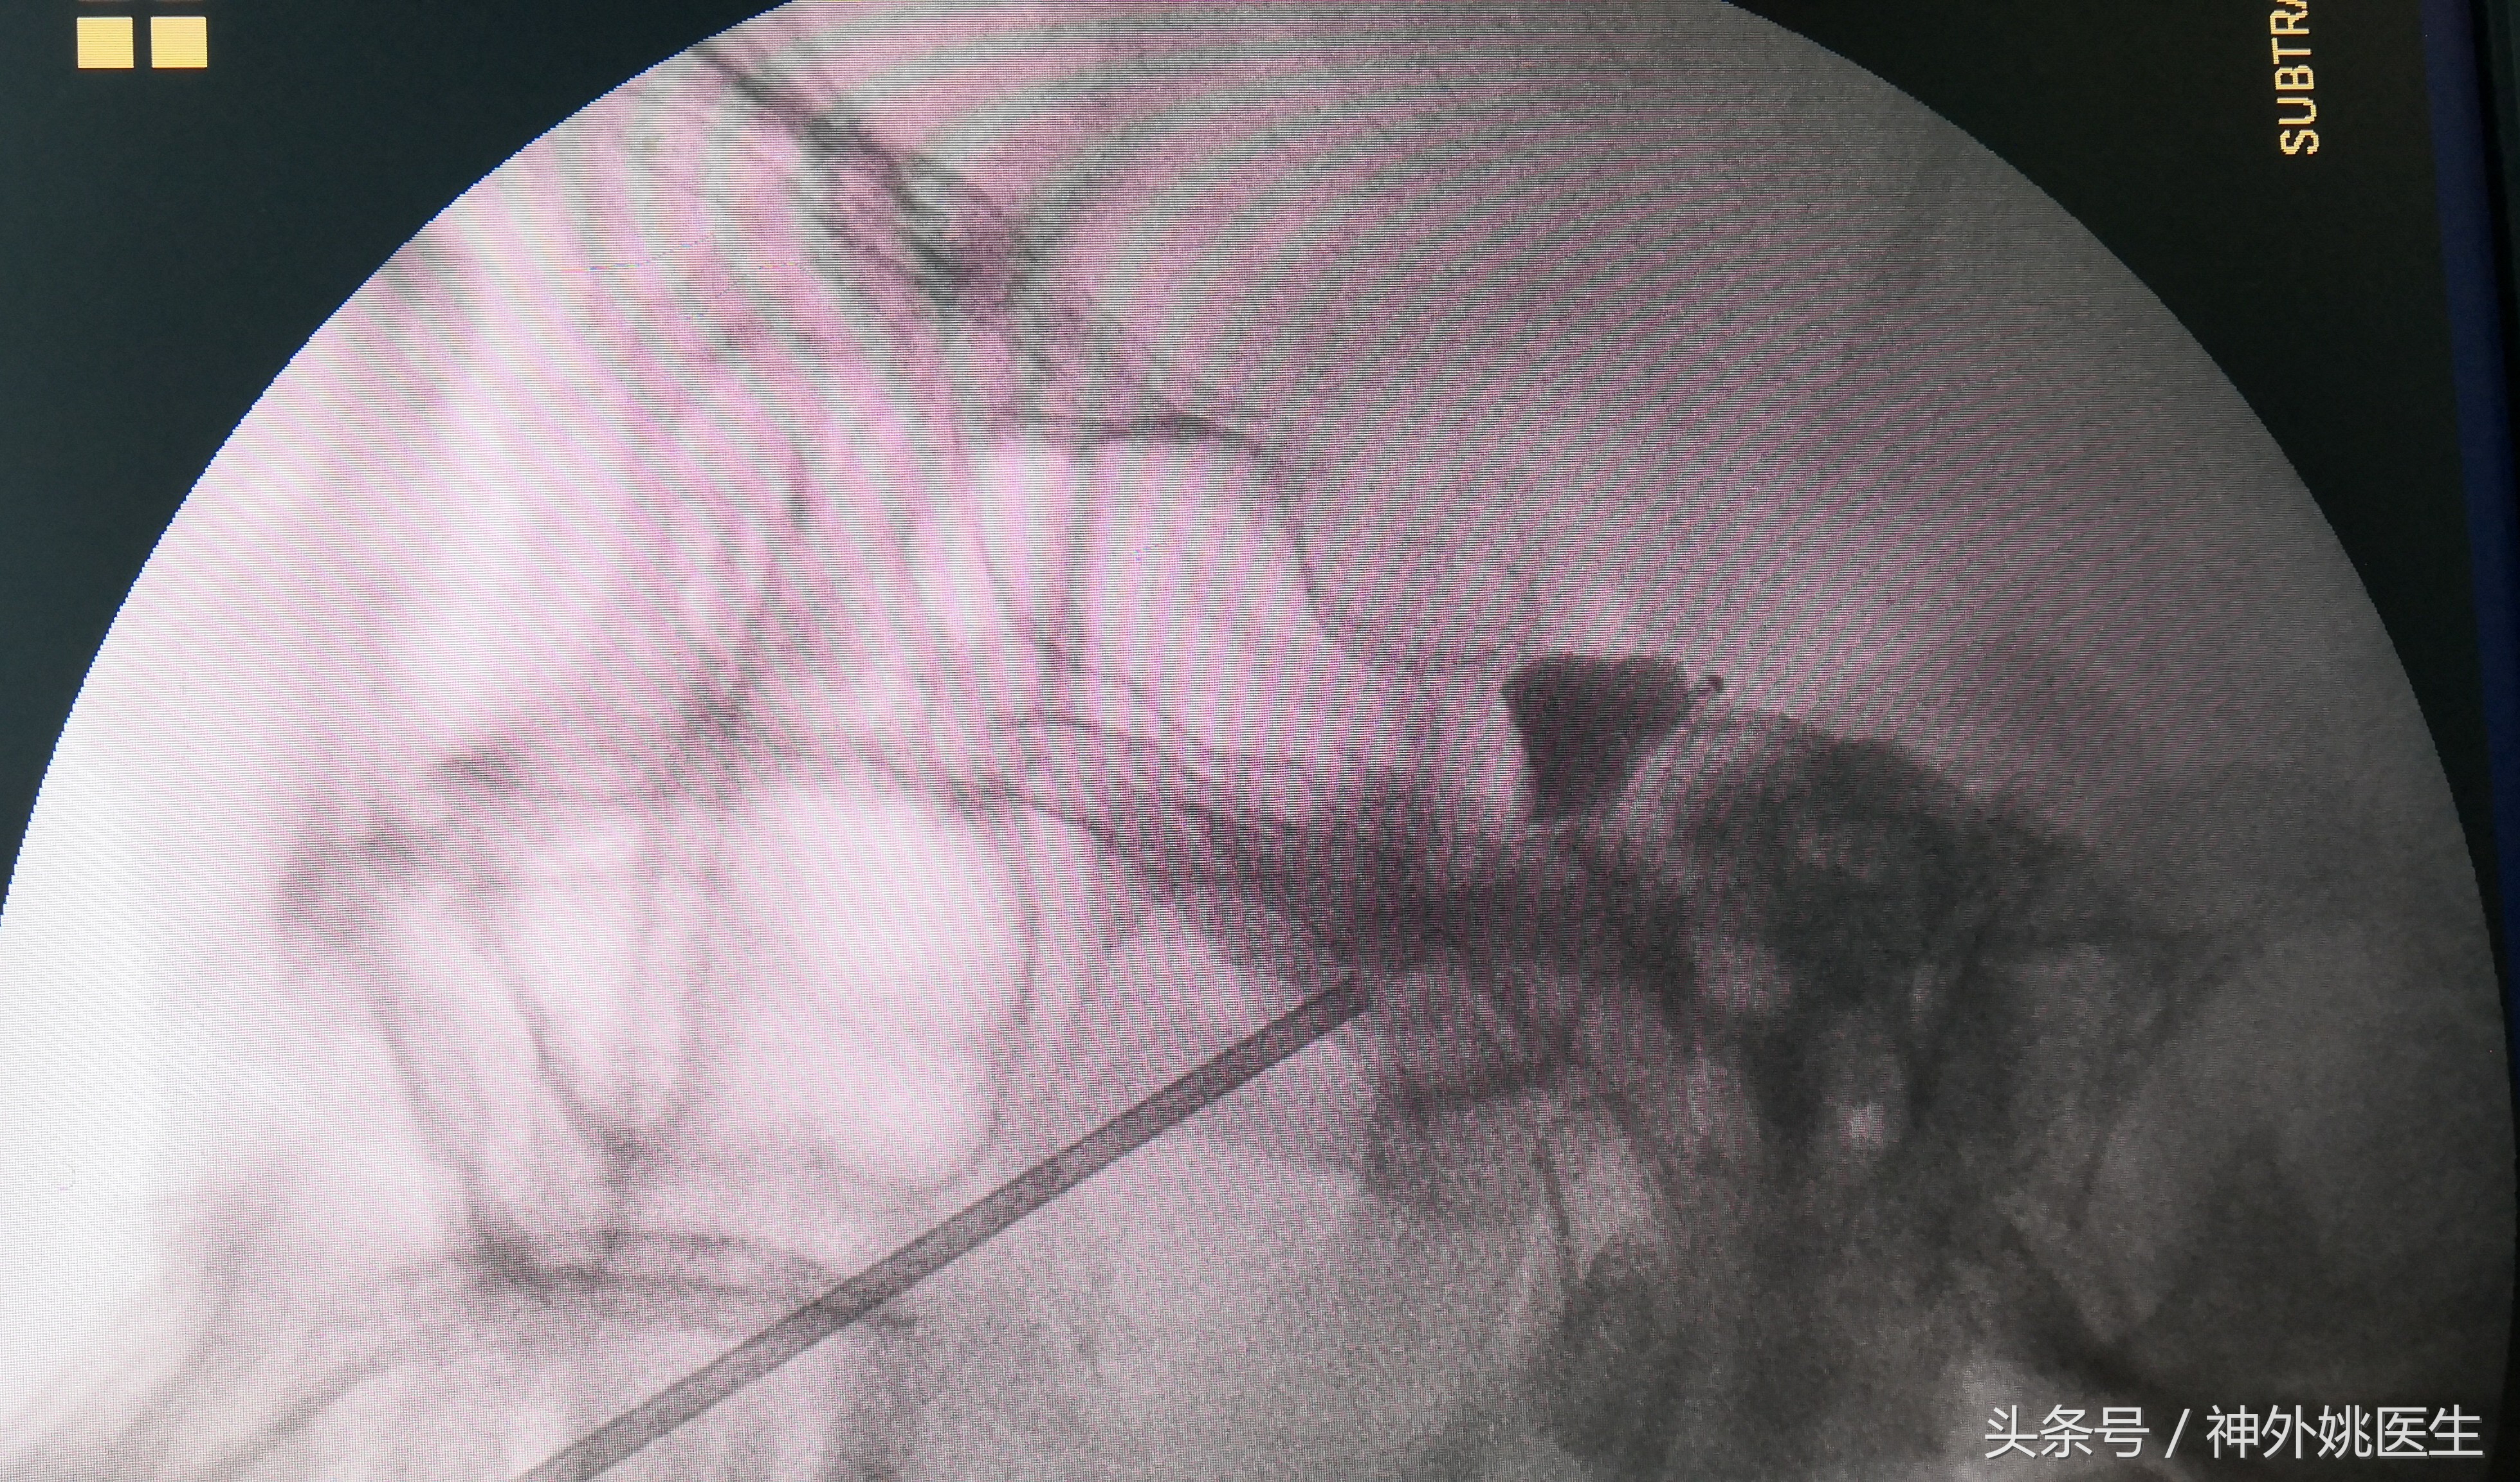

4、充盈球囊,压迫三叉神经半月节(图5-7):

图5 注入造影剂0.6ml,球囊呈梨形,压迫3分钟。

图6 球囊呈梨形膨胀,提示球囊位于Meckle`s囊。

图7 鸭梨写真